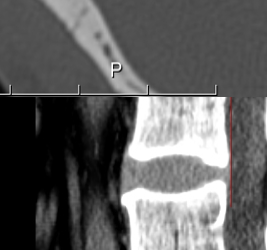

Radiologie - Echographie - Mammographie - Scanner - IRM

Scanner, IRM, échographie, radiographie... Injection d'iode, de gadolinium...